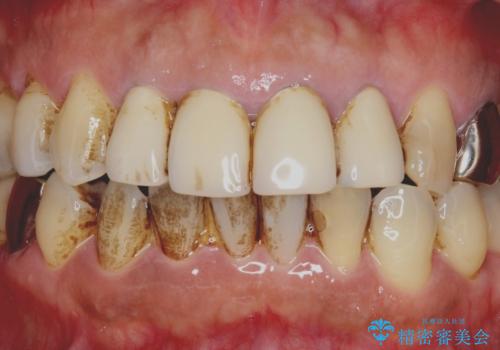

- 10数年前に治療した上顎前歯のクラウンをやり替え、審美性を回復したいと希望され来院されました。

X線写真より問題のなかった根管治療は行わず、クラウンを除去し仮歯でを装着したのちジルコニアクラウンを製作していきます。

茶しぶの目立つ下顎前歯はPMTCを行うことで歯の自然な白さを回復しました。